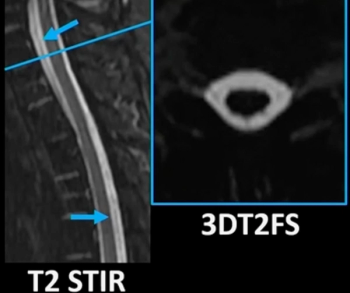

In a recent lecture at the American Roentgen Ray Society (ARRS) 2023 Annual Meeting, Andrew Callen, M.D., discussed a variety of imaging features associated with cerebrospinal fluid (CSF) leaks, the diagnostic utility of the Bern score as well as the merits of 3D T2FS MRI and dynamic computed tomography myelography.